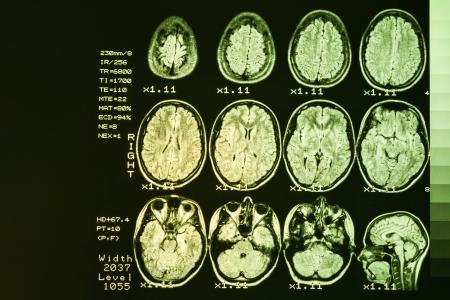

L’autophagie, une nouvelle cible médicamenteuse pour traiter la maladie de Huntington dès ses débuts : dans cette revue de la littérature, les chercheurs discutent les preuves croissantes du rôle central de l'autophagie dans la maintenance synaptique et des effets de la perturbation de l'autophagie sur les changements cognitifs précoces caractéristiques de la maladie. Les auteurs rapportent ainsi des données pathologiques et d'imagerie chez des patients porteurs de mutations de la protéine Huntingtine (mHtt), ainsi que des données issues d’animaux modèles, qui suggèrent qu'un dysfonctionnement synaptique peut survenir très tôt dans la maladie, bien avant la mort cellulaire. Ces changements synaptiques se manifestent notamment par des altérations de la plasticité synaptique et donc par des troubles ou déficits cognitifs. Cette perturbation de la signalisation synaptique contribue en soi à la mort cellulaire dans la maladie.